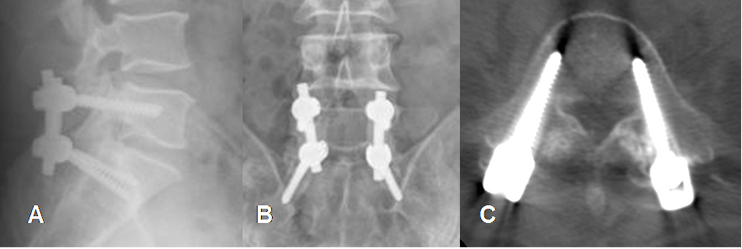

Fig 134. Tornillos normales.

A: Rx lateral y B: Rx AP. Tornillos transpediculares, cuyos extremos se dirigen lateralmente.

C: TAC axial. Buena localización de los tornillos en los pedículos, conservándose íntegras las corticales.